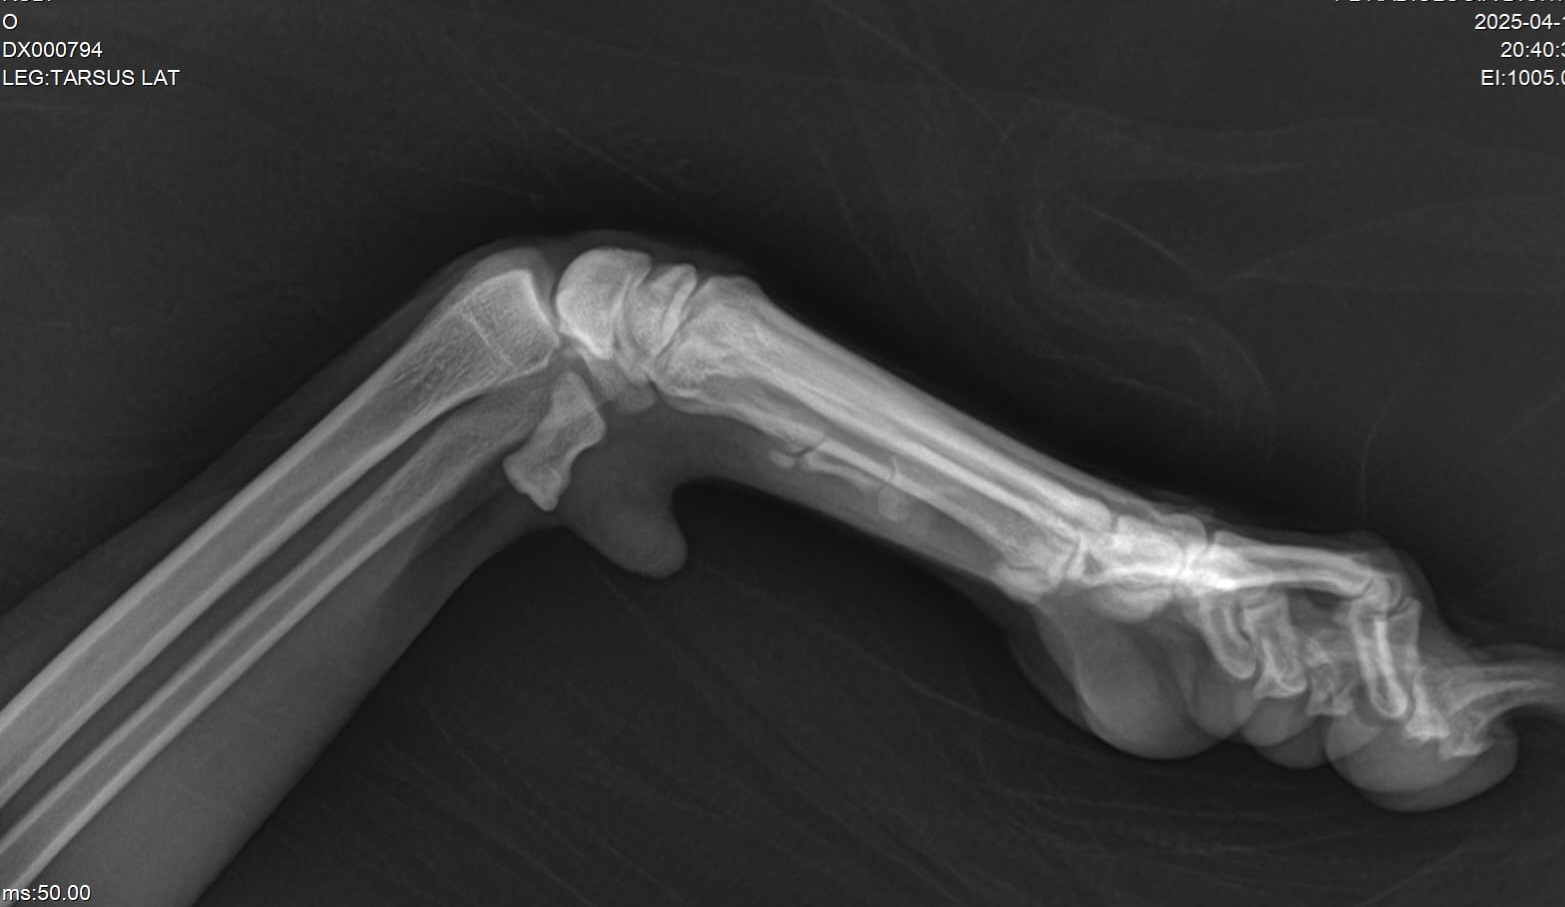

- Radiografías digitales veterinarias

- Equipos digitales portátiles con calidad de centro médico